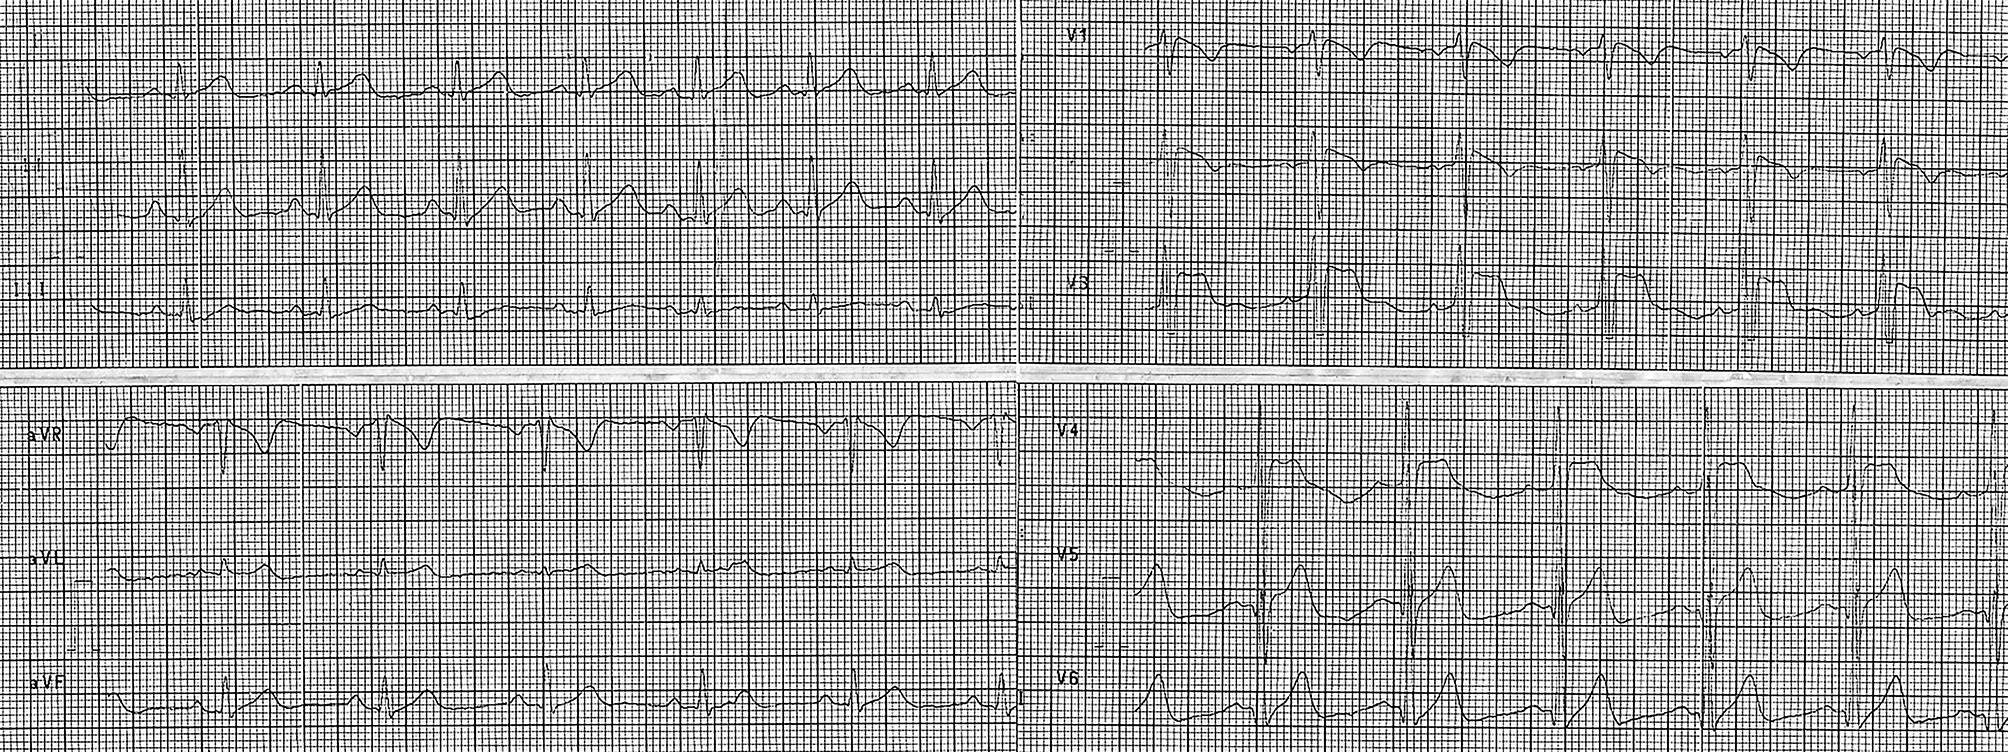

Out-of-hospital electrocardiogram (ECG) shows a sinus rhythm of 85 beats per minute (bpm), narrow QRS complex, and ST-segment elevations in leads V1–V4 (coved morphology in V1–V2), with a terminal negative T wave in V1–V2 (Fig. 1). ECG findings could be suspicious for acute anteroseptal myocardial infarction, but reciprocal ST-segment changes are lacking. The ECG is also suggestive of a coved-type Brugada-like pattern, and the patient had no history of syncope or any other cardiac symptom, nor a family history of unexplained sudden cardiac death.

Fig. 1

Out-of-hospital ECG at first medical contact